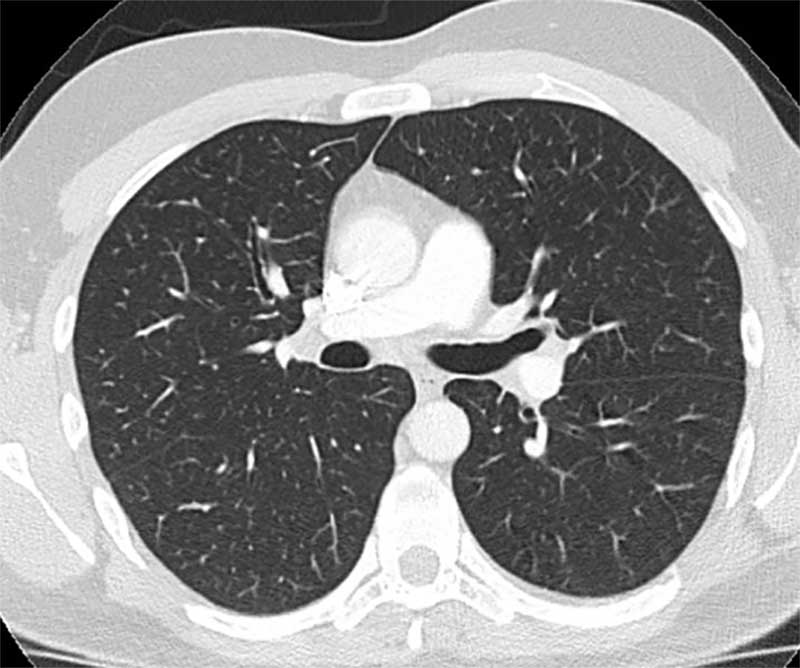

Hochspezialisierte Modalitäten (Volldigitales Röntgen, 80-Zeilen Multidetektor Spiral-CT, 3-Tesla MRT) wenden in ihrer Rekonstruktions-Software sowie nachgeschalteten diagnostische Algorithmen künstlicher Intelligenz an und gewährleisten eine hoch akkurate Diagnostik bei schonender Patientenversorgung. Neben Methoden zur automatischen Detektion und Volumetrie pathologischer Areale kommen Untersuchungsverfahren zur Lungenperfusion und -ventilation zum Einsatz. Die CT-gesteuerte Bronchusnavigation wird neben anderen Methoden als minimal-invasives Biopsieverfahren eingesetzt. Bei diesem Bildfusionsverfahren fungieren hoch aufgelöste CT-Datensätze als interaktive Karte (Roadmap) zur bronchoskopischen Biopsiegewinnung und ergänzen neben der CT-gesteuerten transthorakalen Biopsie die Kryobiopsie und offene Lungenbiopsie-Verfahren.

Die Diagnostik beginnt mit einer professionellen Befragung (Anamnese) und klinischen Untersuchung. Viele Faktoren werden berücksichtigt – u.a. die berufliche und örtliche Umgebung, die Vorgeschichte, Hobbys und die Verwendung legaler oder illegaler Drogen. Standarduntersuchungen sind: Blutuntersuchungen, Lungenfunktionsdiagnostik, Thorax-CT und Bronchoskopie. Eine Lungenbiopsie kann nach Beurteilung des ILD-Boards notwendig werden. Die Biopsie, die Entnahme von Lungengewebe, und nachfolgende histologische Aufarbeitung beim Pathologen gelten jedoch nicht mehr als einzige Methode der Diagnosesicherung. Sie ist – neben klinischer Informationen und Computertomographie – eine von drei validen Methoden, die das ILD-Board gewichtet, heranzieht und abstimmt.